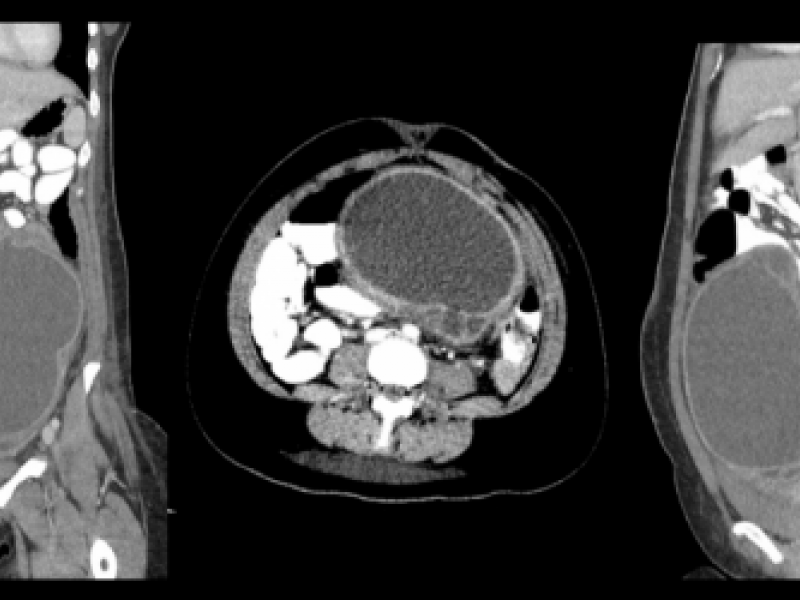

Answer : Tubo-Ovarian Abscess Radiology reported a large